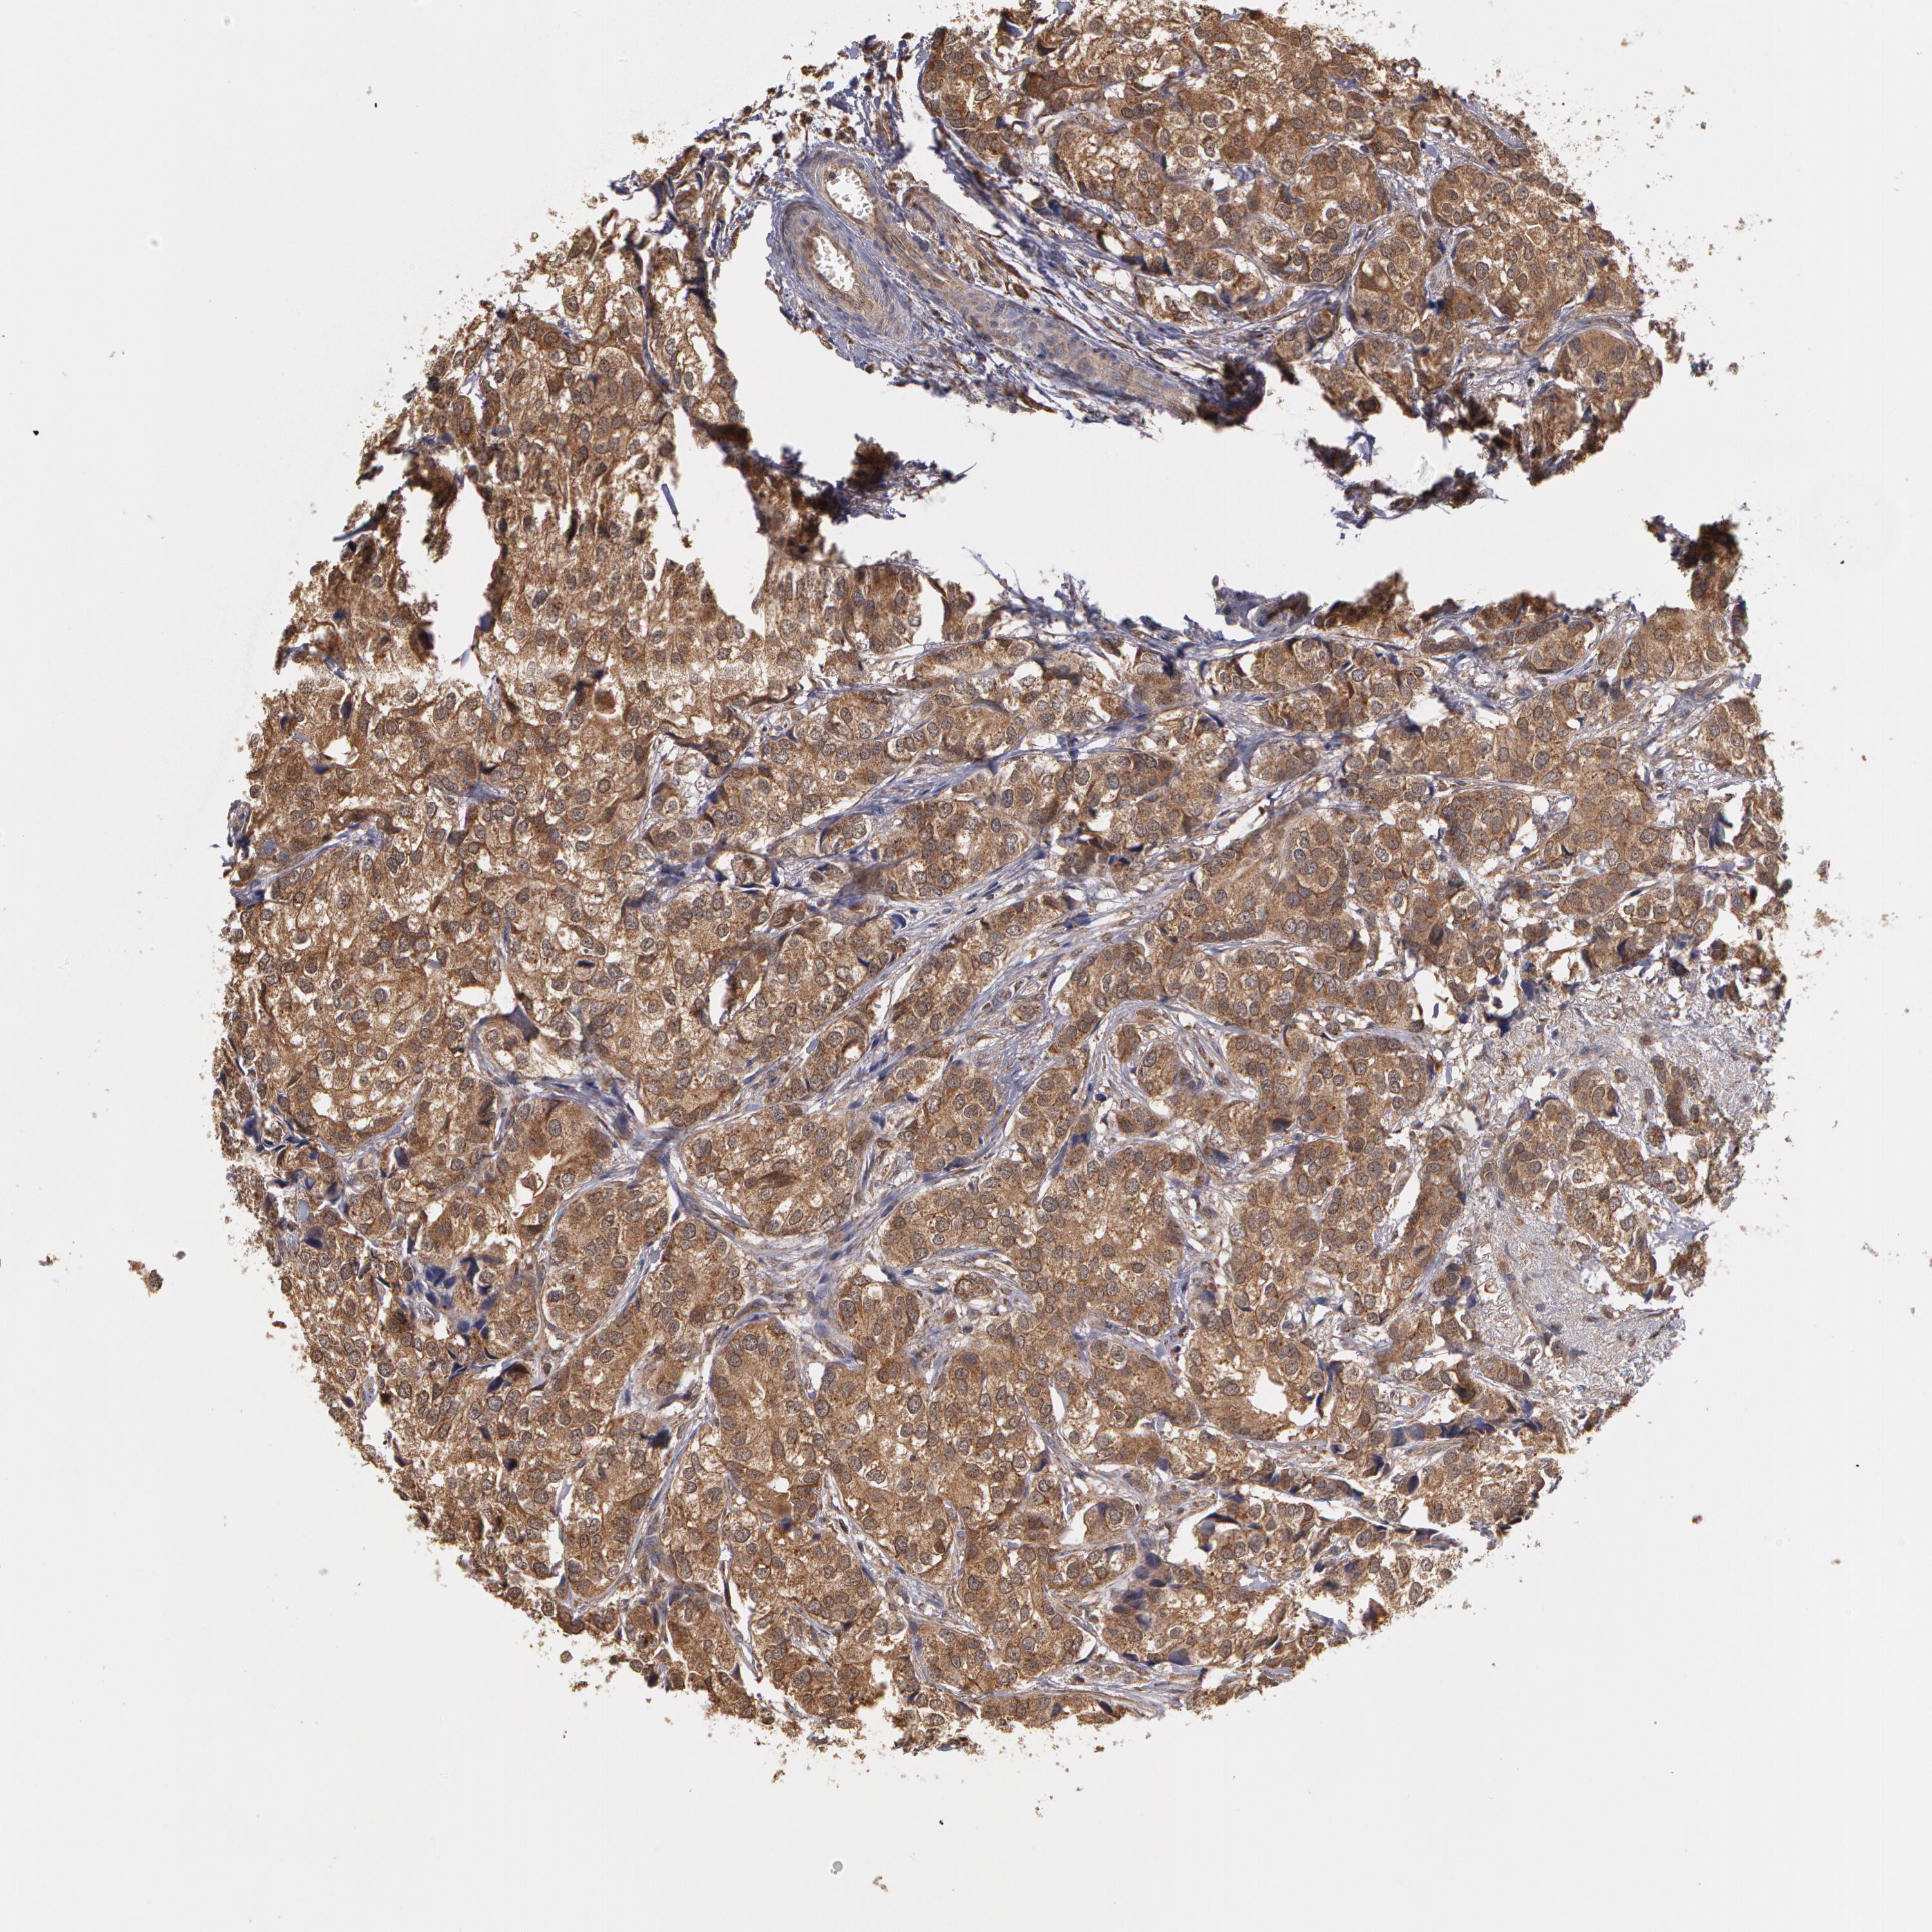

BRCA TCGA BRCA VALIDATION PROTEIN EXPRESSION

ANTIBODIES

AND

VALIDATION